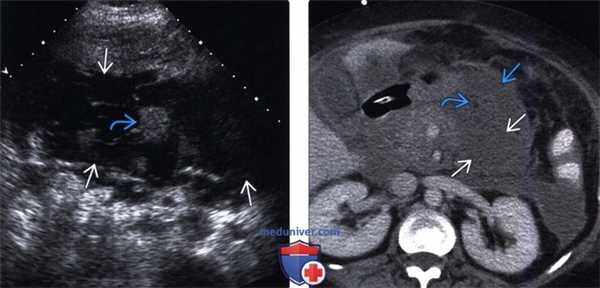

(Левый) На поперечном УЗ срезе брюшной полости визуализируется гетерогенная гипоэхогенная поджелудочная железа, что соответствует картине интерстициального отечного панкреатита. Спереди от тела поджелудочной железы определяется ги-поэхогенная перипанкреатическая жидкость, соответствующая острому скоплению секрета поджелудочной железы.

(Правый) У этого же пациента при КТ с контрастным усилением визуализируется гетерогенная низкоконтрастная поджелудочная железа, что соответствует картине интерстициального отечного панкреатита. Тело поджелудочной железы окружено зоной перипанкреатического отека; кроме того, в области хвоста железы определяется скопление секрета поджелудочной железы.